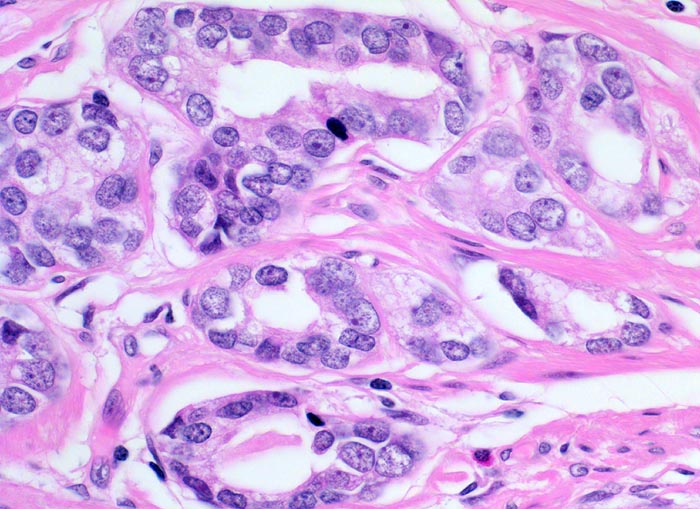

Adenokarzinom der Prostata

Mittelgrosse, gut geformte Karzinomdrüsen ausgekleidet durch ein einreihiges kubisches Epithel ohne Basalzellschicht. Die einzelnen Drüsen sind voneinander durch wenig Stroma getrennt. Die Karzinomzellen haben deutlich vergrösserte hyperchromatische Kerne mit deutlich erkennbaren, aber nicht sehr grossen Nukleolen.

Leicht vergrösserte Prostata. Makroskopisch sind die Karzinomherde als peripher gelegene unscharf begrenzte gelbliche Herde erkennbar. Diese sind palpatorisch derber als das übrige Parenchym.

Aufgrund eines deutlich erhöhten PSA Wertes anlässlich einer Screeninguntersuchung wurde die Prostata biopsiert. In 4 von 6 Stanzbiopsien von beiden Seiten waren Karzinominfiltrate nachweisbar. Daraufhin erfolgte eine radikale Prostatektomie.

400